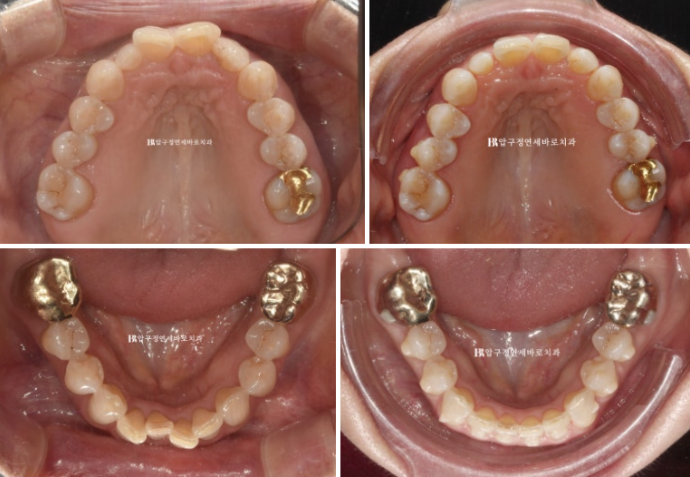

23.09

The lower teeth were also crooked.

Originally, after orthodontic treatment, only the peg lateral tooth was to have its size restored with veneers, but later it was decided to place no-prep laminate veneers on all eight front teeth.

23.09~24.03

The alignment was well established.

24.08

Do you see the space on both sides of the peg lateral tooth?

The intended space for restoring the tooth size was successfully created.